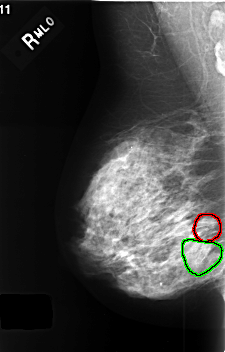

FILE: C_0407_1.RIGHT_MLO.OVERLAY

TOTAL_ABNORMALITIES 2

ABNORMALITY 1

LESION_TYPE CALCIFICATION TYPE AMORPHOUS DISTRIBUTION CLUSTERED

ASSESSMENT 4

SUBTLETY 3

PATHOLOGY BENIGN

TOTAL_OUTLINES 1

BOUNDARY

ABNORMALITY 2

LESION_TYPE CALCIFICATION TYPE PLEOMORPHIC DISTRIBUTION SEGMENTAL

ASSESSMENT 3